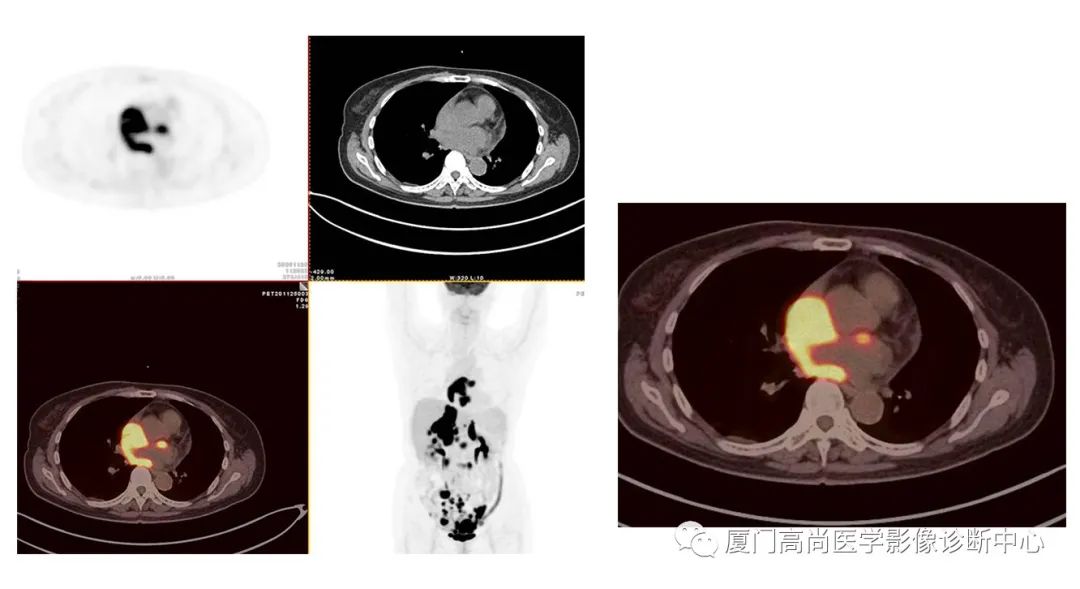

病例2、某女士,62歲,近3個(gè)月來自覺消瘦,無其他自覺癥狀,CT發(fā)現(xiàn)雙側(cè)腎上腺增大,性質(zhì)待定,查血各項(xiàng)腫瘤標(biāo)記物均正常,臨床診斷不清,申請(qǐng)做PET/CT檢查

左心房淋巴瘤病灶

右心房淋巴瘤病灶

PET/CT發(fā)現(xiàn) :左心房、右心房見團(tuán)塊狀FDG攝取增高;雙側(cè)腎上腺增大,F(xiàn)DG攝取增高;膽囊和胃壁結(jié)節(jié)樣FDG攝取增高;小腸多節(jié)段腸壁增厚,F(xiàn)DG攝取增高;腹膜后、腹腔及盆腔多發(fā)淋巴結(jié)腫大,F(xiàn)DG攝取增高;上述考慮為淋巴瘤

經(jīng)腎上腺穿刺活檢 :病理證實(shí)為彌漫大B細(xì)胞淋巴瘤